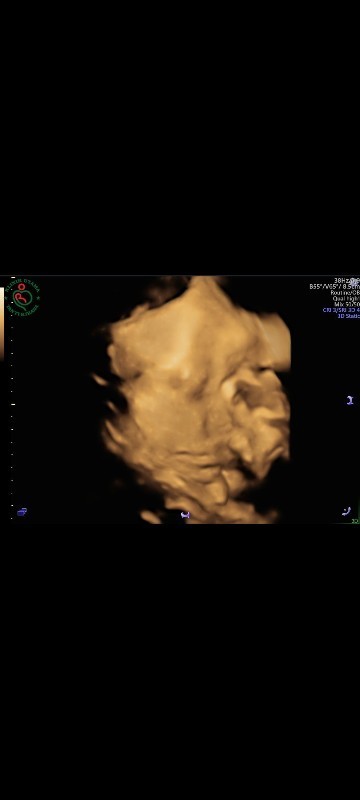

Tentang kehamilan ..

33 itu brapa bulan yah bun pas nya?